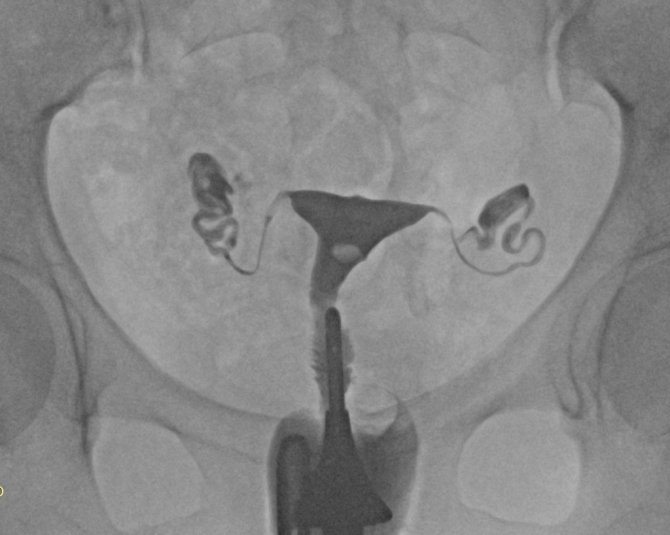

Histerosalpingografi (HSG) olarak isimlendirilen rahim filmi, bebeğin gelişimini tamamladığı rahim yani uterus boşluğu endometrium ile yumurtanın rahime taşındığı tüplerin görüntülenmesini sağlıyor.

HSG ile rahmin kalıtsal sorunları, miyom veya polip gibi kitleleri, düşük, kürtaj veya enfeksiyon gibi nedenlerle olaşabilecek yapışıklıklar ile birlikte tüplerde darlık, tıkanıklık veya genişleme gibi sorunların tespit edildiğini ifade eden Doruk Sağlık Grubu Yıldırım Hastanesi Grişimsel Radyoloji uzmanı Doç. Dr. Nurullah Doğan, "HSG en çok kısırlık veya düşük durumlarında kadın hastalıkları ve doğum uzmanı tarafından istenir. Daha önce kullanılan yöntemlerin hiç biri HSG'nin verdiği bilgilerin tamamını veremez" diye konuştu.

İşlem rahim ağzında verilen ilacın rahim boşluğu ve tüpleri doldurması sonucu şeklinde uygulandığını ifade eden Doç. Dr. Nurullah Doğan, "Elde edilen radyolojik görüntüler incelenerek teşhis konulur. Verilen ilaç renksiz ve kokusuz olup organ ve dokular üzerinde bir zararı yoktur. Tetkik için rahmin en uygun olduğu zaman adet bitiminden sonraki 3 ve 7 inci günler arasıdır. Hasta işlem sonrası aynı gün içinde normal yaşamına dönebilir. Utanma veya korku gibi sebeplerde ise isteyen hastalarda işlem hafif ve kısa süreli bir anestezi yani sedasyon altında yapılabilir. Gebelik, pelvik enfeksiyon, aşırı kanama ve yakın zamanda yapılan uterus veya tüpler ile ilgili ameliyat olması durumu HSG işlemi yapılmaz. HSG sadece teşhis koyulmasını sağlayan değil, bazı hastalarda tedavi edici bir işlemdir. Yüksek basınçla verilen kontrast madde tüplerdeki mukus benzeri engelleyici yapıları temizler. Bu sebeple kısırlık gelişen hastalarda tüplerin temizlenmesi sonrası yumurtalar rahim boşluğuna ulaşarak gebelik sağlanır" dedi.